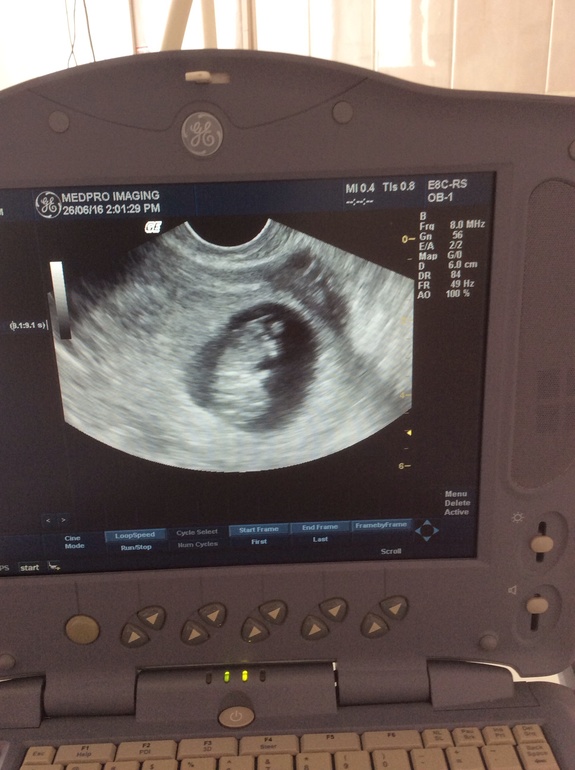

Итак, некоторое время назад А мне звонит и заговорщически сообщает, что хочет срочно попасть на прием). По совершенно невероятной причине - у нее задержка - ну это не новость- но она внезапно решила сделать тест на беременность - и вооот это ноооовость))). Новости сейчас уже 20 недель))), уже можно делиться))))